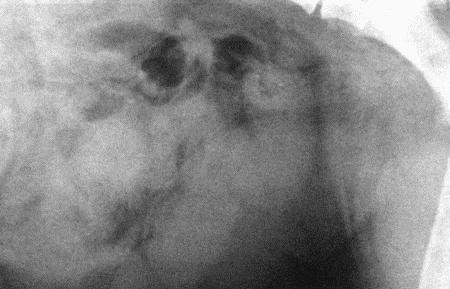

При рентгенографии в латеральной проекции (фиг. 4.17) увеличенная, наполненная жидкостью матка выявляется как затемнение в венитральном отделе брюшной полости. Кишечник смещен, и расстояние между мочевым пузырем и прямой кишкой увеличено. Матка почти всегда увеличена. Следует отметить, что беременная матка между 4 и 6 неделями, т. е. на стадии, когда еще не заметны скелеты зародышей, может давать картину, сходную с пиометрой. Одним из существенных недостатков рентгенографии является необходимость применения седативных препаратов.

Фиг. 4.17.

Латеральная рентгенограмма матки при пиометре у суки. Видны равномерно контрастные увеличенные рога матки